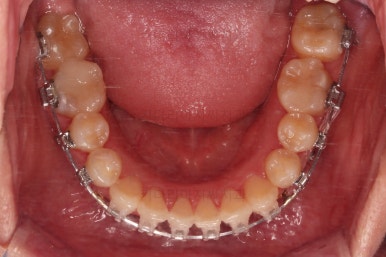

초진 시 입안의 모습입니다.

이미 썩어서 부러진 치아도 몇 개 보이고요.

많이 삐뚤어진 치아쪽은 양치가 힘들어 이미 많이 썩어 있는 상태에 덧니쪽은 잇몸도 많이 내려간 상태였습니다.

말그대로 교정치료 뿐만 아니라 전반적인 치료가 필요한 상황이었습니다.